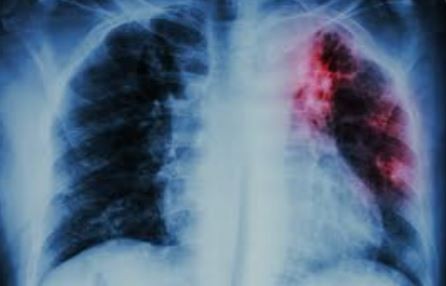

Desde el CONICET explican que la tuberculosis es una enfermedad infecciosa que se transmite de persona a persona a través del aire, cuando alguien enfermo tose o estornuda. De acuerdo con cifras oficiales en el mundo, cada día, cerca de 3.500 personas pierden la vida por esta patología y cerca de 30 mil se contagian de esta enfermedad prevenible y curable. En la Argentina, en 2024 se notificaron alrededor de 16.600 casos de tuberculosis, de los cuales aproximadamente el 84 % correspondieron a personas en edad productiva (20 a 44 años).

Actualmente, hay un tratamiento efectivo que consiste en la toma de una combinación de antibióticos por un período de 6 a 24 meses. Sin embargo, uno de los principales desafíos para frenar la tuberculosis es el diagnóstico. A diferencia de otras bacterias, Mycobacterium tuberculosis (agente infeccioso de la tuberculosis) crece muy lento, por lo que los métodos tradicionales para su detección demoran de seis a ocho semanas y si bien hay tecnologías más rápidas son muy caras y difíciles de implementar.